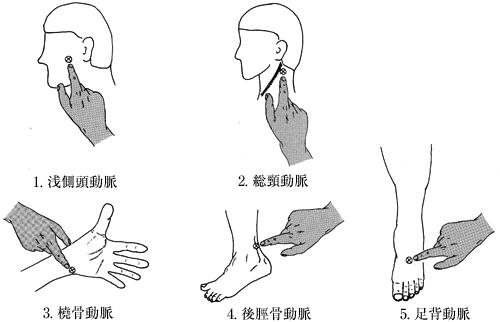

57歳の男性。脳梗塞による左片麻痺。発症後3週経過。Brunnstrom法ステージは上肢I、手指I、下肢II。座位保持が30分可能となった。左肩関節亜脱臼と手部に中等度の腫脹がある。麻痺側上肢の管理として適切でないのはどれか。

1

1

2

2

3

3

4

4

5

5